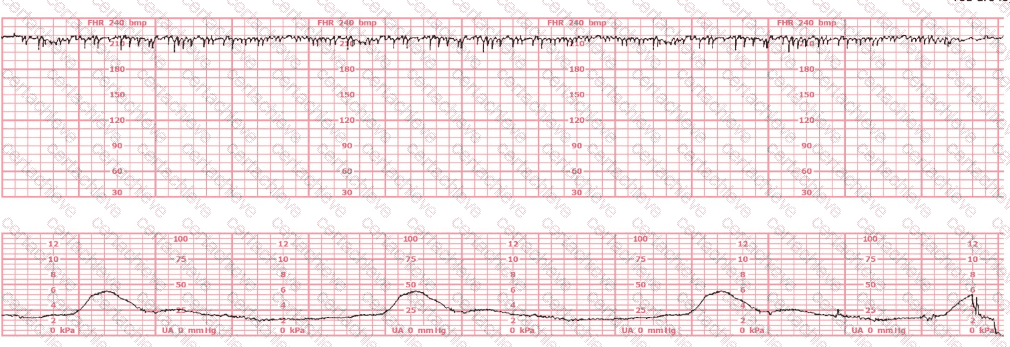

QUESTION DESCRIPTION:

This is a fetal heart rate tracing of a multiparous woman whose cervix is 7 cm dilated on admission. The most likely cause for this pattern is:

The tracing shows a clear relationship between uterine activity and fetal heart rate changes :

The uterine activity strip demonstrates very frequent contractions with little resting time between them , exceeding five contractions in 10 minutes , averaged over a 30-minute window.

NCC and NICHD define tachysystole as “more than 5 contractions in 10 minutes, averaged over 30 minutes, regardless of whether the labor is spontaneous or stimulated.”

As uterine activity intensifies and becomes excessively frequent, the fetal heart rate strip begins to show:

Progressive decrease in baseline

Recurrent decelerations with gradual onset and recovery

Reduced variability in the latter portion of the strip

This pattern is consistent with uteroplacental insufficiency caused by excessive uterine activity (tachysystole). NCC and AWHONN emphasize that tachysystole can result in decreased uterine blood flow and fetal oxygenation, leading to late or prolonged decelerations and eventual bradycardia if not corrected.

Why the other options are less likely:

A. Placental abruption Typically associated with maternal symptoms (pain, vaginal bleeding, firm/boardlike uterus) and often a sustained increase in resting tone or a hypertonic contraction , not simply very frequent contractions. These maternal findings are not described in the vignette.

B. Rapid fetal descent Usually causes variable or early decelerations related to head compression, but the tocodynamometer would not necessarily show this degree of contraction frequency. The lower strip here clearly highlights excessive contractions as the primary problem.

Thus, the tracing’s FHR abnormalities are best explained by tachysystole , making C. Tachysystole the most appropriate answer.